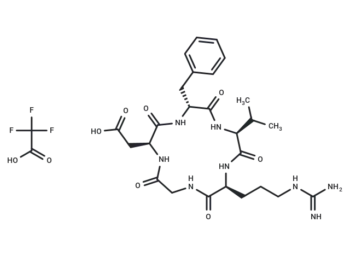

– [C@@H](CC1=CN=CN1)(NC([C@@H](NC([C@@H](NC([C@@H](NC([C@@H](NC(CNC([C@H](CCCCN)N)=O)=O)CC(N)=O)=O)CO)=O)C)=O)CC(C)C)=O)C(N[C@H](C(N[C@H](C(N[C@H](C(N[C@H](C(N[C@@H](CC2=CN=CN2)C(NCC(N[C@@H](CC3=CN=CN3)C(N[C@H](C(NCC(N[C@H](C(N[C@H](C(N[C@H](C(N[C@H](C(N[C@H](C(N[C@H](C(N[C@H](C(N[C@@H](CC4=CC=C(O)C=C4)C(NCC(N[C@H](C(N[C@H](C(N[C@H](C(N[C@H](C(N[C@H](C(N[C@H](C(N[C@H](C(N[C@@H](CC5=CN=CN5)C(NCC(O)=O)=O)=O)CC(N)=O)=O)CCC(N)=O)=O)CCSC)=O)[C@@H](C)O)=O)C(C)C)=O)CC(N)=O)=O)C)=O)=O)=O)CCCNC(=N)N)=O)C(C)C)=O)CC(C)C)=O)[C@@H](C)O)=O)CCC(N)=O)=O)[C@H](CC)C)=O)CS)=O)=O)CC(C)C)=O)=O)=O)=O)CCC(N)=O)=O)CO)=O)C)=O)C(C)C)=O